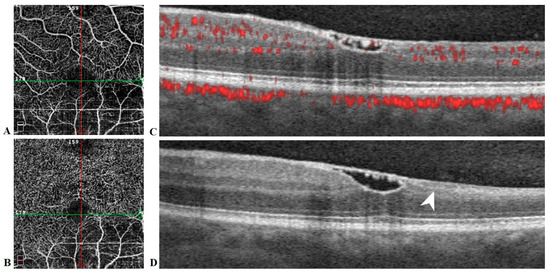

At 11-week follow-up, visual acuity in the left eye had returned to 20/20. Funduscopic exam was significant for complete resorption of blood and a residual wrinkly yellow sheen over the central macula. Humphrey visual fields remained stable. SD-OCT revealed a bridging membrane over the foveal depression. OCT-A (AngioVue; Optovue Inc., Fremont, CA, USA) was limited by artifact but suggested decreased retinal vascular bed density in the inferior macula (Figure 6).

Figure 6. Optical coherence tomography angiography (OCTA) en face images (A,B) and spectral domain OCT B-scans (C,D) of the left eye at 11 weeks follow-up. Decreased vessel density of the superficial (A) and deep (B) retinal capillary plexuses is noted inferiorly in the area of arterial occlusion. A contiguous membrane with mild residual hyper-reflective hemorrhage underneath traverses the foveal depression (C,D). Vertical (D) OCT shows significant thinning of inner retinal layers of the inferior macula (arrowhead).